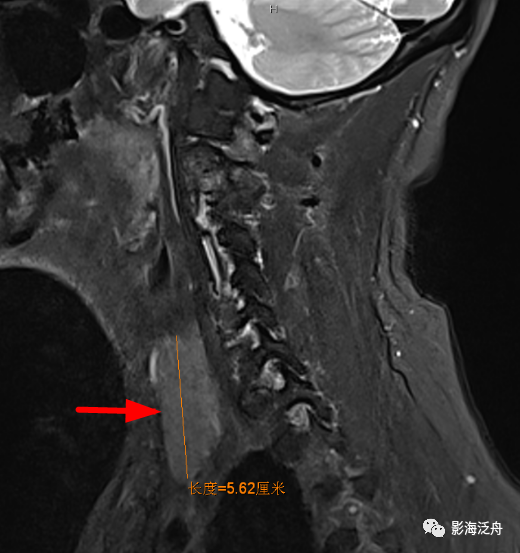

乳腺癌

术后患者,枢椎骨质信号异常,随访证实为骨转移。随着肿瘤患者越来越多,行颅脑MR检查排除脑转移的检查也逐渐增多,不要只顾着在脑子里面找转移灶,周围的结构也应该观察一下。

矢状位上另一个需要观察的就是齿状突的高度,异常增高往往是颅底凹陷症导致的(红线为钱氏线)。